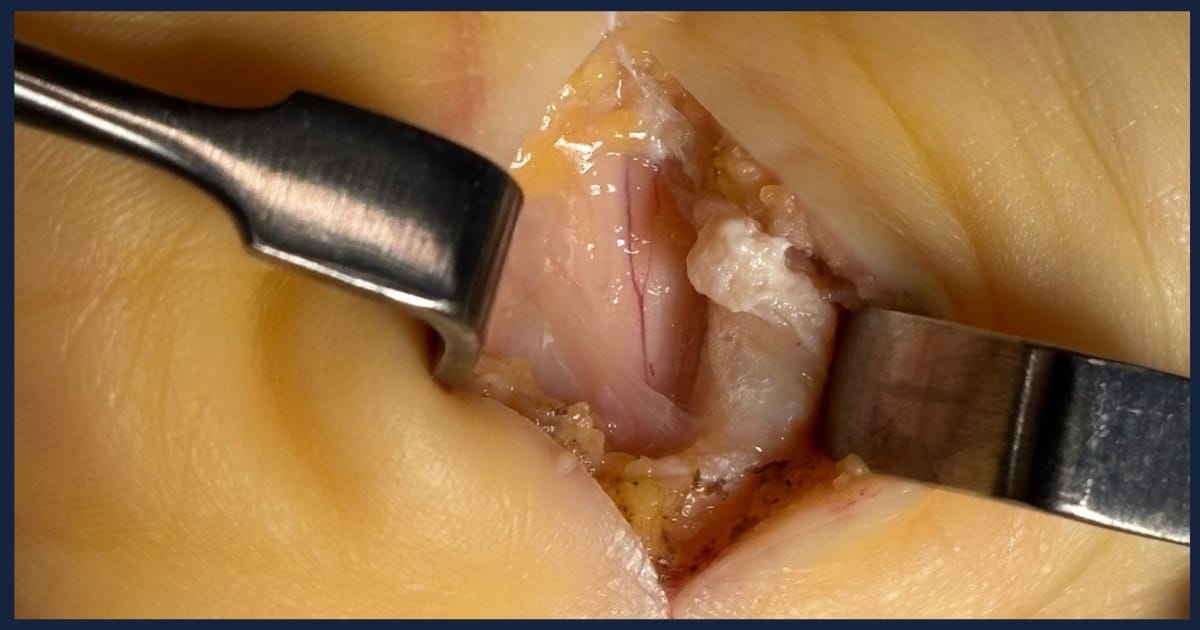

Observamos un ligamento anular anterior del carpo muy engrosado, fibrótico y con restos blanquecinos de la infiltración corticoidea que le practicaron hace 1 mes. El nervio presenta un signo de flushing positivo con revascularización clara de los vasos nervorum. No se aprecian bien los límites nerviosos por encontrarse rodeado de sinovitis (de hecho drenó espontáneamente mucho líquido sinovial claro de las vainas flexoras de la porción distal del antebrazo)

Practicamos un ALAAC asociada a una sinovectomía de tendones flexores superficiales en el canal y un vaciado de líquido sinovial por expresión.

En este caso, el ligamento anular anterior del carpo también está engrosado aunque menos fibrótico que en el caso anterior. El nervio está adherido al ligamento. El flushing no se recupera del todo: se para en el área nerviosa marronácea que corresponde con su máximo acintamiento. Ese área corresponde a la zona de compresión máxima y que el flushing se pare allí es signo de sufrimiento del perineuro (que es por donde discurren los vasa nervorum).

Practicamos un ALAAC asociada a una exoneurolisis del nervio para promover al máximo la descompresión de la zona neural dañada.

El ligamento anular anterior del carpo no estaba ni engrosado ni fibrosado: era tejido cicatricial normal. Todo el contenido del canal carpiano estaba englobado por sinovitis que lo circunvolucionaba. Procedimos a una sinovectomía inicial.

Tras la sinovectomía encontramos una fibrosis perineural de tejido duro que era fácilmente disecable con pinzas y tijera. Procedimos a una exoneurolisis para retirar todo el tejido fibrótico.

En ese momento era claramente visible una zona de fibrosis circunscrita, de tejido similar al ligamento anular anterior del carpo, que comprimía los nervios digitales al pulgar e índice . No estaba adherida al nervio y era fácilmente resecable.

Tras la resección se observaron estructuras nerviosas con aspecto macroscópico normal ( sin zonas estenóticas en “reloj de arena” en el área comprimida, sin edema proximal a la zona de compresión, sin cambios en la turgencia y brillo normales).